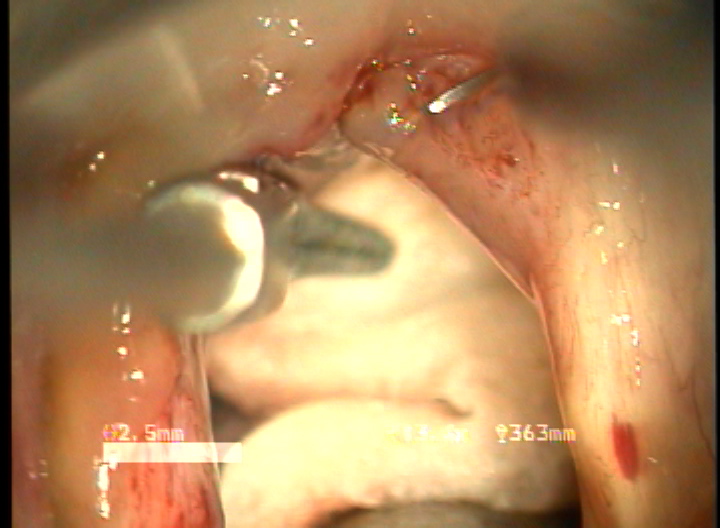

double rotational microflap laryngoplasty 수술 동영상... more >

결과 : 음성개선에 대한 주관적인 평가로서 수술전 Voice Handicap Index는 평균 19.7 에서 술후 11.5로 감소하였다. 공기역학적인검사상 성문하압은 5.5에서 4.5로 감소되었으며, 최대발성시간 13.7에서 16.1로 증가되었다. 음성분석검사상 sPPQ, sAPQ, NHR, SPI, DSH가 모두 통계학적으로 유의하게 감소하였다. 후두스토로보스코피검사상 모든 례에서 재발의 징후없이 성대점막파동의 의미있는 호전이 나타났다. 합병증으로 1례에서 염증성 육아종형성이 관찰되었으나 미세피판의 괴사나 탈락은 관찰되지 않았다.

결론 : 전성문횡격막의 새로운 수술방법으로서 double rotational microflap laryngoplasty는 일차수술로 만족스러운 음성학적 치료결과를 얻을 수 있는 매우 유용한 술식이라 사료된다.